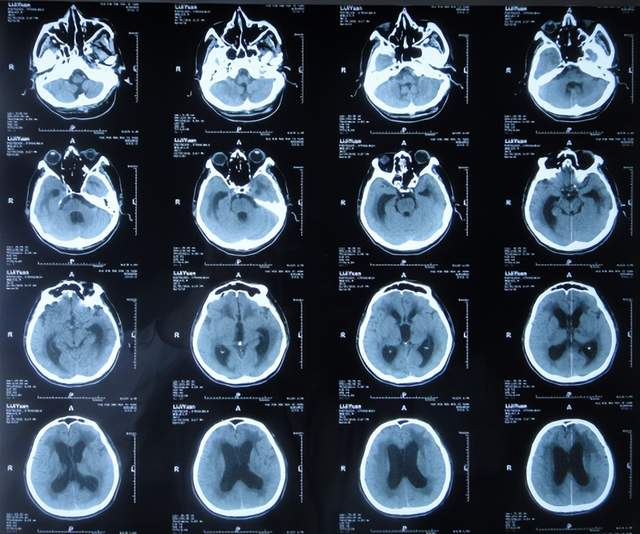

2022年2月22日(入院治疗6天),意识变清,能遵嘱抬起手(图-16)。

图-16:2022年2月22日

2022年3月1日(入院治疗13天),病情进一步改为:意识便完全正常,大小便变正常,扶着能坐起,言语交流变基本正常(图-17);头颅CT示脑室变小(图-18)。

图-17:2022年3月1日

图-18:2022年3月2日头颅CT

2022年3月4日(入院治疗16天),由入院时喂流食变得能自己进食(图-19)。

图-19:2022年3月4日

2022年3月10日(入院治疗22天),在俩人搀扶下能自己迈步走路(图-20)。

图-20:2022年3月10日

2022年3月11日(入院治疗23天),进行了脑室腹壁外引流术。

2022年3月18日(入院治疗30天),走路进一步改善:在一人搀扶下能走路(图-21)。

图-21:2022年3月18日

2022年4月7日(入院治疗50天),查头颅CT示脑室引流术后状态,未见异常(图-22)。

图-22:2022年4月7日头颅CT

2022年4月27日(入院治疗70天)家属要求出院回家休养。出院时:携带脑室腹壁外引流管;精神变得挺好,能自己站立但自己走路不稳,体重较入院时明显增加,入院时消瘦病态的体型已基本恢复正常状态(图-23);出院时头颅CT示脑室引流状态(图-24)。

图-23:出院时

图-24:出院时头颅CT

三、第2次在李小勇脑脊液科治疗过程和结果

出院后4个月即2022年8月30日,为了做脑积水分流术,再次来到李小勇脑脊液科,入院时:精神状态良好,能自己走路了稍不稳(图-25);头颅CT示脑室引流术术后状态(图-26)。

图-25:2022年8月30日

图-26:2022年8月30日头颅CT

完善各项检查后于2022年9月15日,进行了脑室腹腔分流术(图-27)。

图-27:2022年9月15日头颅CT

脑室腹腔分流术后13天即2022年9月28日出院。出院时:走路进一步变稳,身体其他均正常(图-28)。

图-28:2022年9月28日